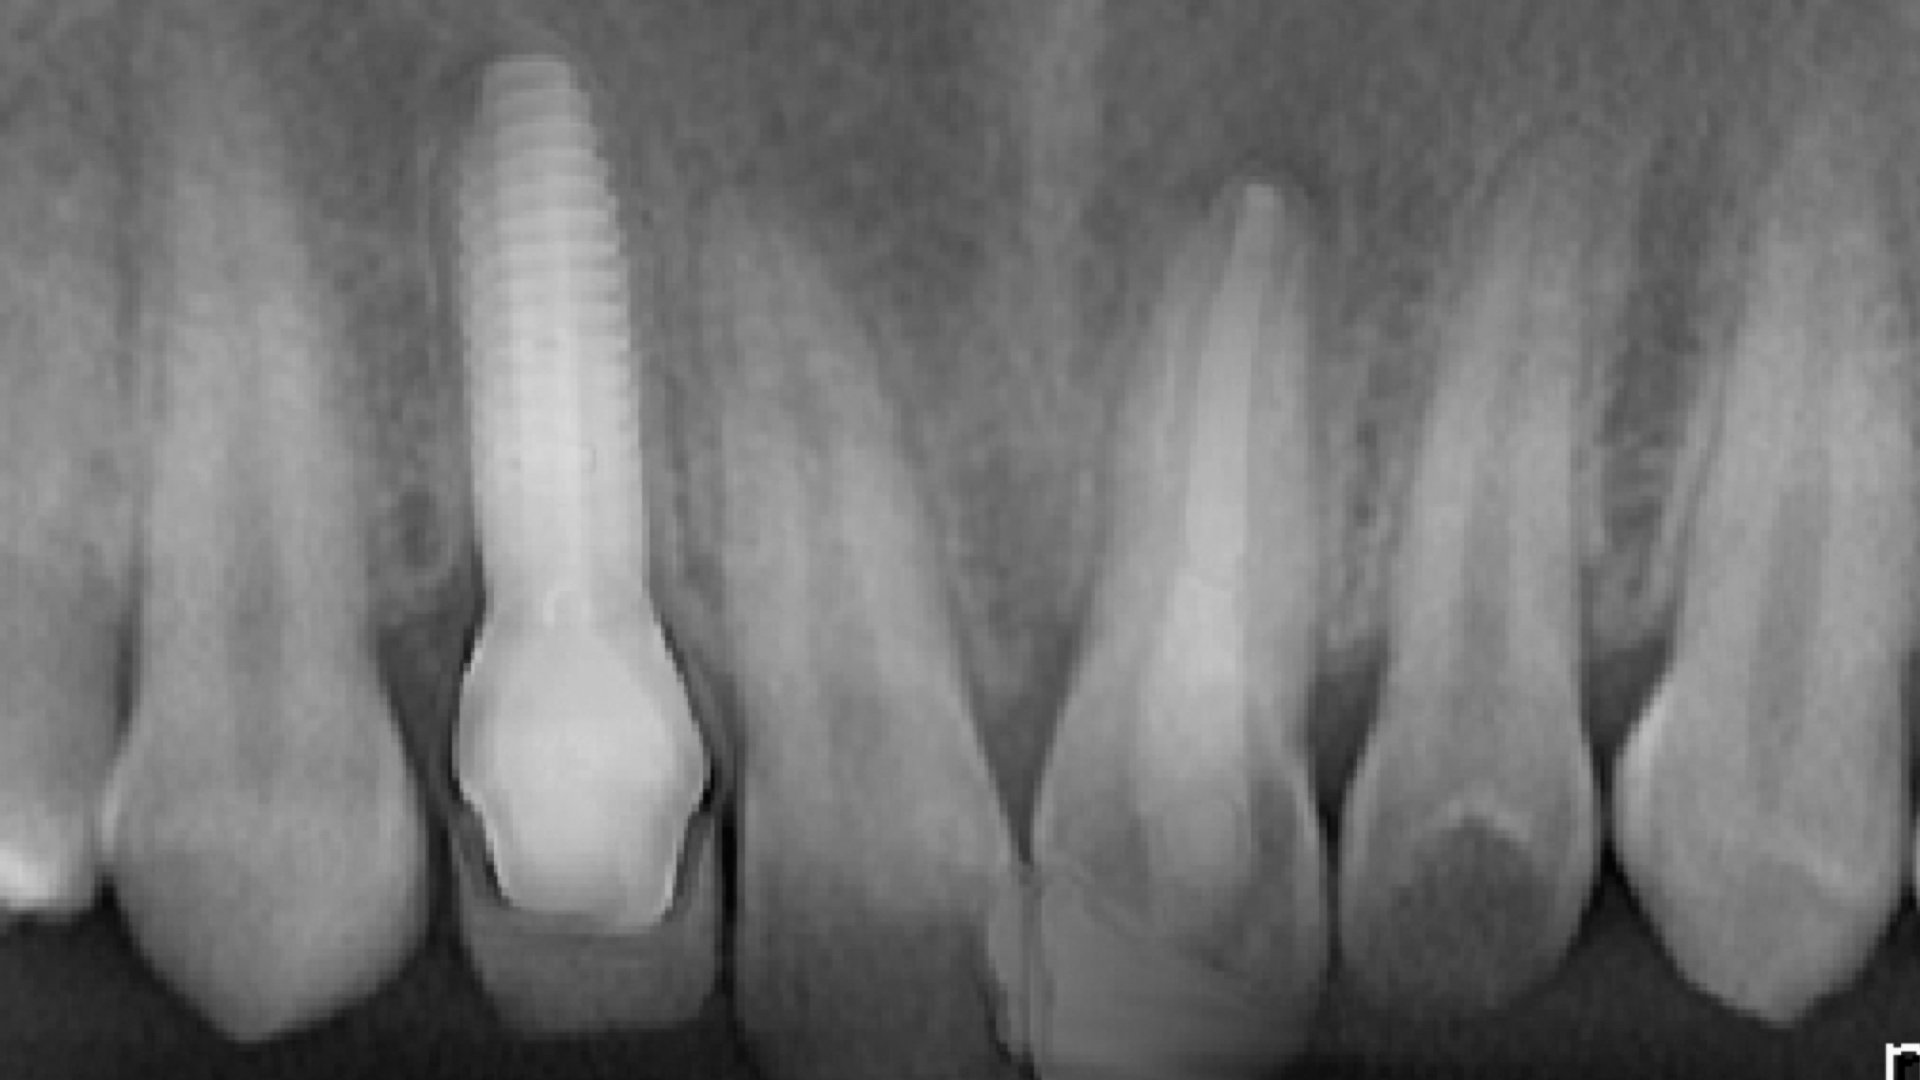

Marian a suferit un accident cu bicicleta. Din păcate, acesta a fost foarte grav şi a dus la un traumatism al dinţilor frontali. Dintre aceştia, unul nu a mai putut fi salvat şi de aceea a fost nevoie de inserarea unui implant dentar. Restul dinţilor au avut nevoie de tratamente pe canal şi refacere a formei anatomice. În locul dintelui unde s-a inserat implantul s-a pus la final o coroană integral-ceramică pe un stâlp hibrid din zirconiu, iar restul dinţilor afectaţi au putut fi reconstituiţi din compozit, ajutându-l să revină la o viaţă normală. Tratamentul acesta a fost ales ca fiind varianta optima şi minim-invazivă pentru acest pacient în vârstă de 18 ani. Nu ştim dacă pasiunea pentru ciclism i-a revenit, dar în mod cert, i-am resuscitat zâmbetul.